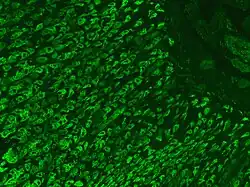

- In pernicious anemia, autoantibodies directed against parietal cells or intrinsic factor cause a reduction in vitamin B12 absorption. It can be treated with injections of replacement vitamin B12 (methylcobalamin, hydroxocobalamin or cyanocobalamin).